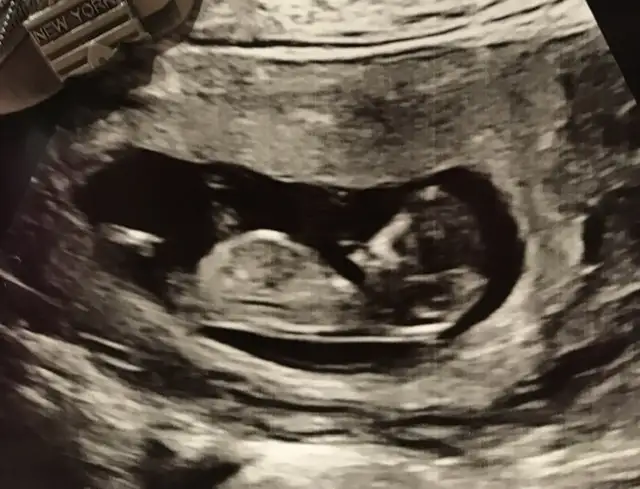

Bizede bi tahmin yapar mısınız ???

Günaydın Ikra meyra Ikra meyra 1 kızım bir oğlum var bakalım hangisinin yanına eş olcak 😊 11 de ki usg ye de erkek gibi demiştin ben hala anlamıyorum resimlerden bir şey kafa yapısına göre mi yoksa nub a göre mi yorumluyorsun , 1 ay sonra sonraki kontrolüm . Tekrar görürşürüz bakalım sonuçları bildiririm😘